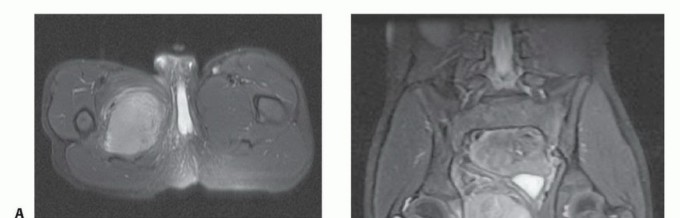

- التشخيص: يتطلب فحصًا شاملاً، تصويرًا متقدمًا (MRI، CT)، وخزعة نسيجية لتأكيد التشخيص وتحديد نوع ودرجة الورم.

- العلاج: يتضمن عادةً الجراحة (الاستئصال الواسع مع الحفاظ على الطرف)، وغالبًا ما يتبعها علاج إشعاعي أو كيميائي لتقليل خطر التكرار أو انتشار الورم.